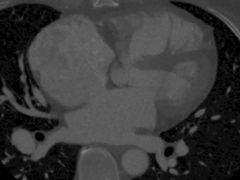

2017-05-11 关键字:大多数患者在童年期不呈现明显临床症状,直到进入青年期才开始表现出易疲乏,劳累后气急、心悸等症状。且对肺循环压力升高的病人更加容易反复发作,引起呼吸道感染和肺炎等疾病的发生,需及时对患者进行手术治疗,即......